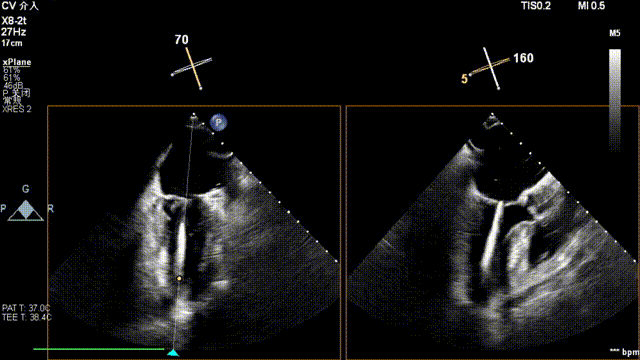

全麻后,二尖瓣夹合器系统在心前区的肋间切开3-4CM小切口,暴露心脏的心尖位置,送系统送入左心房,顺利到达病变二尖瓣区域。在经食道超声辅助下,术者通过反复评估二尖瓣反流位置、抓捕位置、反流程度,首先在2偏3区位置处于二尖瓣闭合线垂直进行巧妙夹合。在2区靠近3区位置处植入了1枚ValveClamp®MVC-IIf夹,最终评估评估反流降至轻度,平均跨瓣压差降至2mmHg,手术取得圆满成功。

术中超声(关键步骤)

最终在A3P2位置夹合,前叶夹合量10mm,后叶夹合量8mm,剩余瓣口面积3.45cm²,平均跨瓣压差2mmHg,反流基本消除。